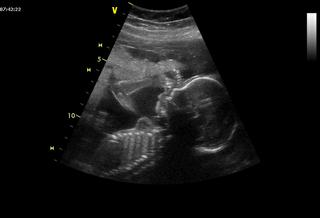

@lola22 Tak držím pěsti na čtvrtek 😉 Dělali mi ho přes břicho a od té doby už stále jen přes břicho. PK na velikost plodu nemá vliv, ale spíš jestli ti to právě nepočítají jako mě od poslední ms, tím pádem ti to nevychází, pokud jsi měla nějak posunutou ovulaci. Jelikož jsi po IVF tak víš přesně na den, kdy jsi měla ovulaci a když od ní odečteš 14 dní tak od toho datumu si vypočítej stáří mimi.

Holky teď mi připadá, že to pěkně letí, není to tak dlouho co jsem na UTZ pozorovali jen malé bublinky 🙂